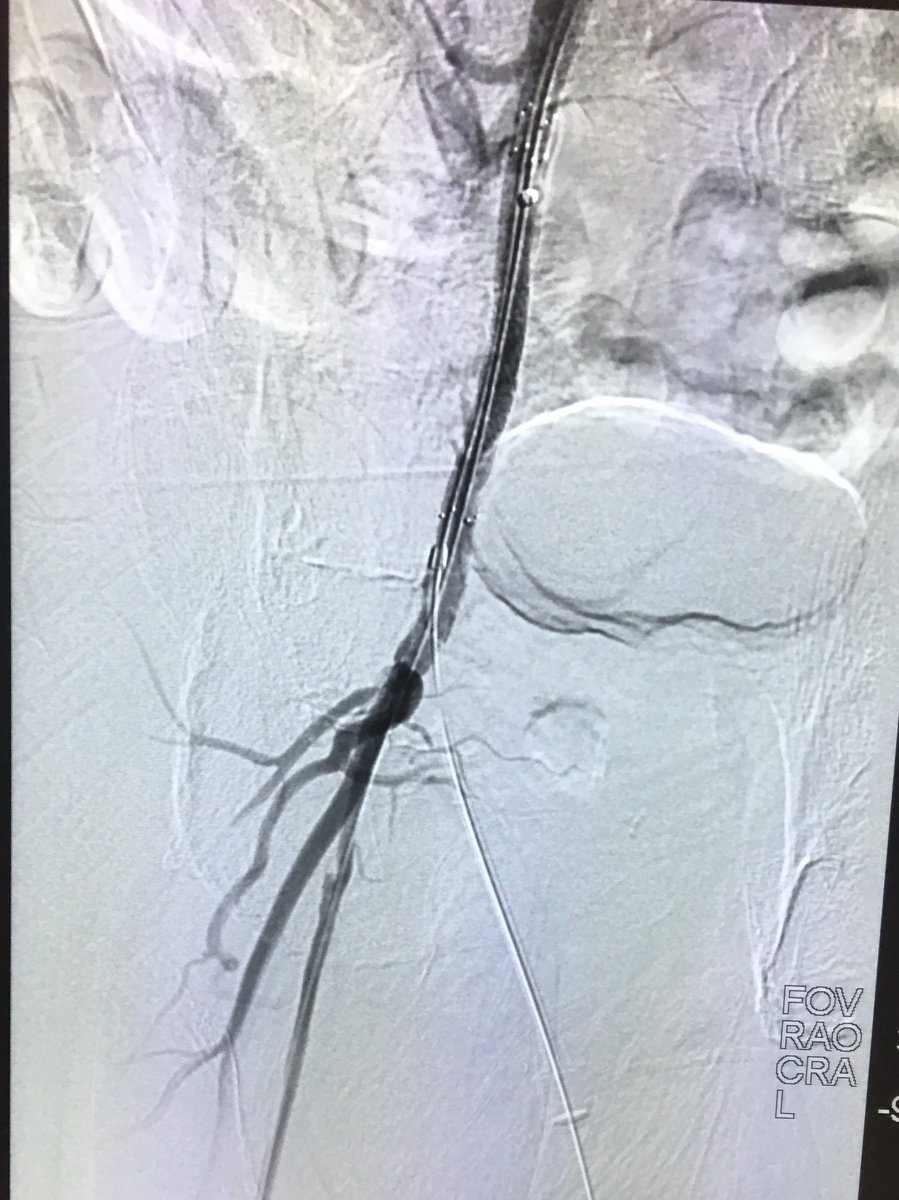

Right external iliac occlusion. Wire went subintimally antegrade and retrograde. Outback catheter deployed to re-enter true lumen. Successful drug-eluting stent placement UICOMP Radiology SIR RFS #SIR #IRad #TwittIR #JVIR Society of Interventional Radiology

Right external iliac occlusion. Wire went subintimally antegrade and retrograde. Outback catheter deployed to re-enter true lumen. Successful drug-eluting stent placement <a href="/UICOMPRadiology/">UICOMP Radiology</a> <a href="/SIRRFS/">SIR RFS</a> #SIR #IRad #TwittIR #JVIR  <a href="/SIRspecialists/">Society of Interventional Radiology</a>